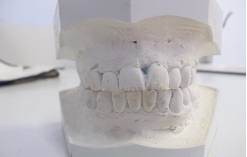

An image of molds below

Records taking, Diagnosis, Treatment Plan, Classification and Fee.

In this phase Cephalometric X-Rays(above), Panoramic X-Rays(below), Orthodontic Photos(Interoral and Extraoral) and Impression(Molds) are made and taken for study purposes.